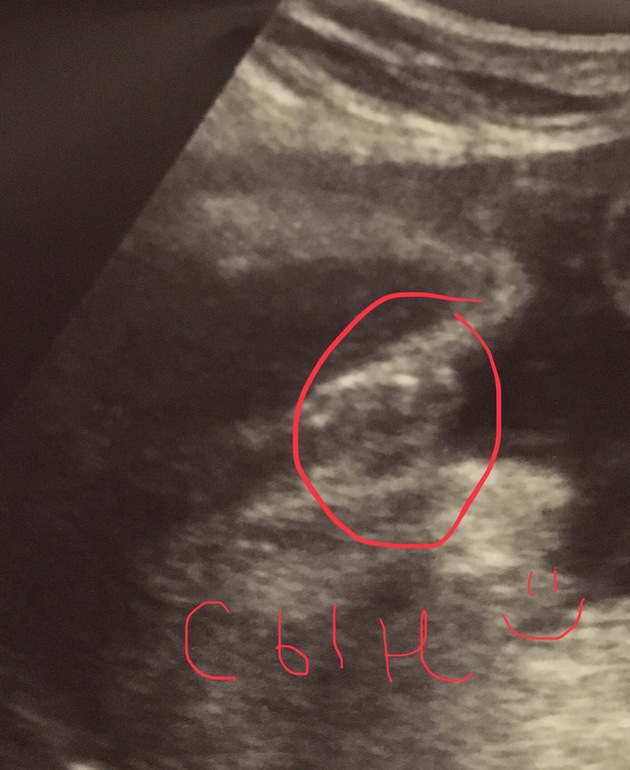

А время то летит) и в роддом уже хочется, и наоборот так удобно, что малыш в пузе, меньше забот! Вчера были на узи и ещё раз подтвердили сыночка, со всех ракурсов рассмотрели)) малыш такой спокойный у меня, всё узи проспал, да и вообще редко буянит. Неужели будет спокойный ребёнок? Весим 850 грамм, рубец около сантиметра по-прежнему, шейка вагинально 45 мм, ну и лежим головкой вниз, как я и думала (пинки выше пупка и давление внизу, когда головкой шевелит). Всё пока нормально, ттт! Надеюсь, проблем и не будет.